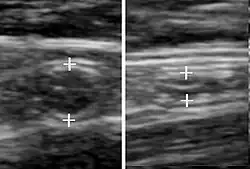

Abdominal ultrasonography, preferably with doppler sonography, is useful to detect appendicitis, especially in children. Ultrasound can show the free fluid collection in the right iliac fossa, along with a visible appendix with increased blood flow when using color Doppler, and noncompressibility of the appendix, as it is essentially a walled-off abscess. Other secondary sonographic signs of acute appendicitis include the presence of echogenic mesenteric fat surrounding the appendix and the acoustic shadowing of an appendicolith.[59] In some cases (approximately 5%),[60] ultrasonography of the iliac fossa does not reveal any abnormalities despite the presence of appendicitis. This false-negative finding is especially true of early appendicitis before the appendix has become significantly distended. Also, false-negative findings are more common in adults where larger amounts of fat and bowel gas make visualizing the appendix technically difficult. Despite these limitations, sonographic imaging with experienced hands can often distinguish between appendicitis and other diseases with similar symptoms. Some of these conditions include inflammation of lymph nodes near the appendix or pain originating from other pelvic organs such as the ovaries or Fallopian tubes. Ultrasounds may be either done by the radiology department or by the emergency physician.[61]

-

Ultrasound showing appendicitis and an appendicolith.[62]

Ultrasound showing appendicitis and an appendicolith.[62] -

Ultrasound of a normal appendix for comparison. -

A normal appendix without and with compression. Absence of compressibility indicates appendicitis.[59]